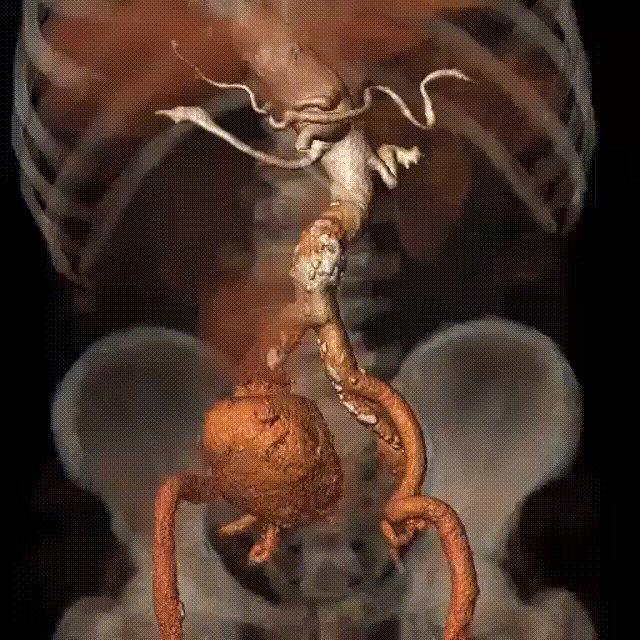

术前CTA红色箭头为动脉瘤及血肿

术前CTA提示右侧髂内动脉瘤伴巨大破口